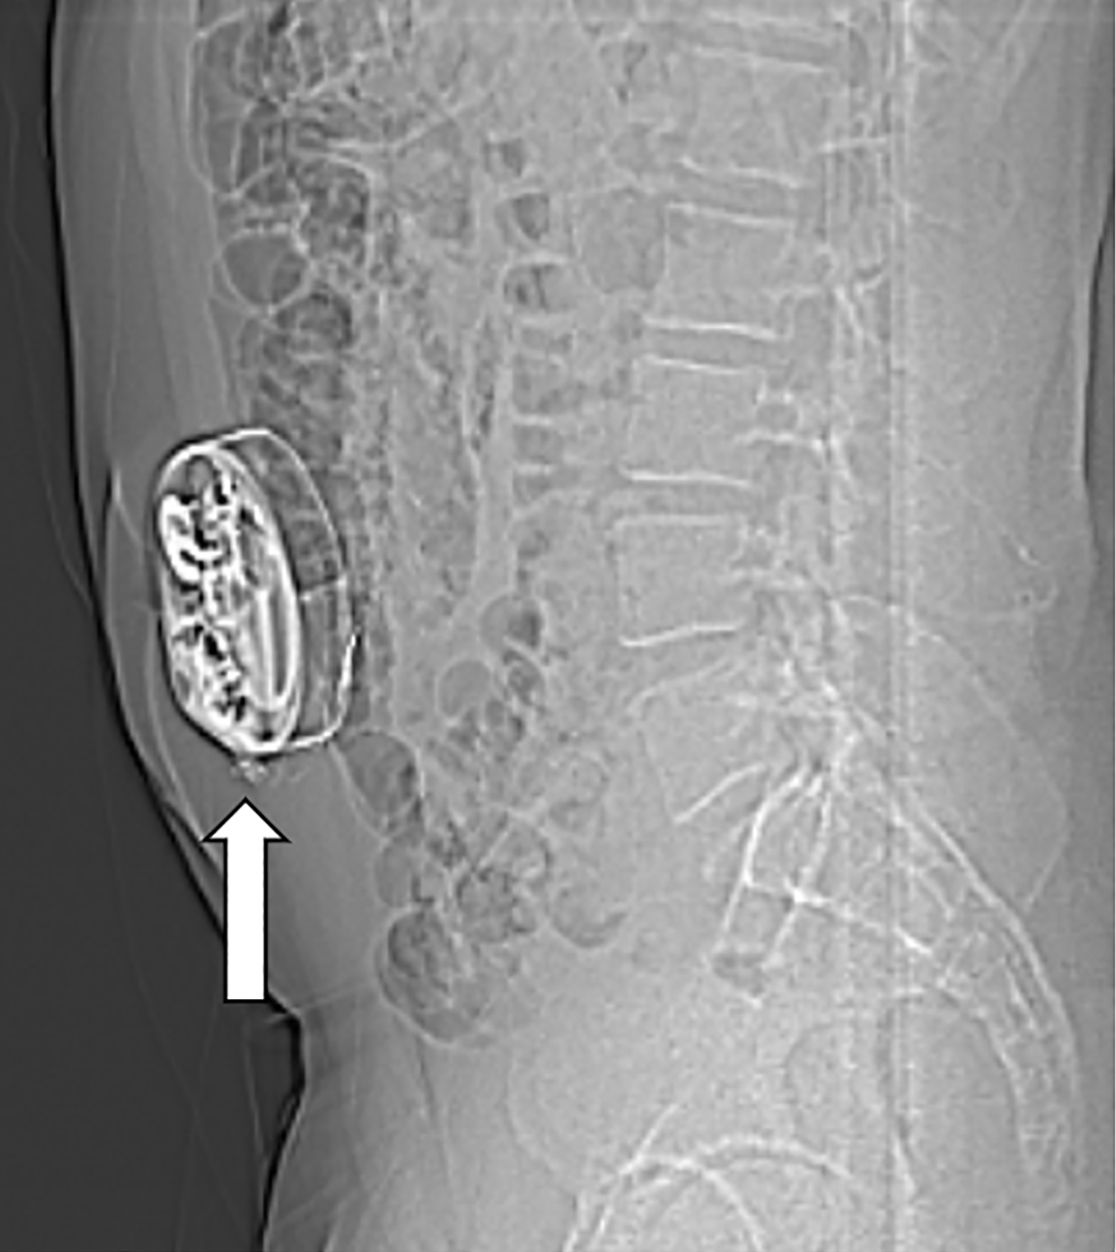

Bei Patienten mit schwerer Spastik oder chronischen Schmerzen, die nicht ausreichend auf herkömmliche medikamentöse Therapien ansprechen, kann die Implantation einer Schmerzpumpe eine effektive Lösung darstellen. Diese Pumpe ermöglicht die direkte Abgabe von Schmerzmitteln oder muskelentspannenden Medikamenten in den Nervenwasserraum (intrathekal), was eine deutlich gezieltere Wirkung mit geringeren Nebenwirkungen ermöglicht als bei in Tablettenform eingenommenen Medikamenten.

Das Pumpensystem besteht aus einem kleinen Schlauch, welcher in den Nervenwasserraum eingebracht wird und mit der Pumpe verbunden ist. Die Pumpe wird meist am Bauch unter der Haut implantiert und ermöglicht, dass die Dosierung der Medikamente exakt an die Bedürfnisse angepasst werden kann. Es ist eine regelmäßige Wiederbefüllung der Pumpe mit den Medikamenten notwendig, was ähnlich wie bei einer Blutabnahme von außen erfolgt.

In unserer Klinik bieten wir Ihnen eine ausführliche Beratung, die Implantation sowie die kontinuierliche Nachsorge dieser Therapie, um Ihre Beschwerden bestmöglich zu lindern und Ihre Lebensqualität zu steigern.

Im Nervenwasserraum (Liquor) einliegender Schlauch zur intrathekalen Therapie (Pfeil)

Am Bauch implantierte Medikamentenpumpe (Pfeil)